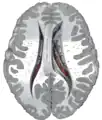

Ventricles of brain and basal ganglia. Superior view, horizontal section, deep dissection

Ventricles of brain and basal ganglia. Close-up of preceding image

Caudate nucleus highlighted in green on transversal T1 MRI images